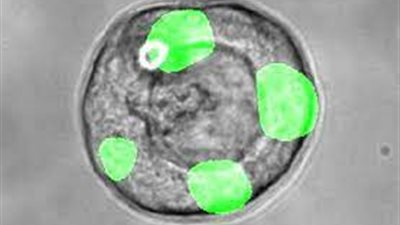

باحثون يكتشفون نوعًا جديدًا من الخلايا في الرئة البشرية بخصائص تجديدية

الثلاثاء 05/04/2022 08:39 ص